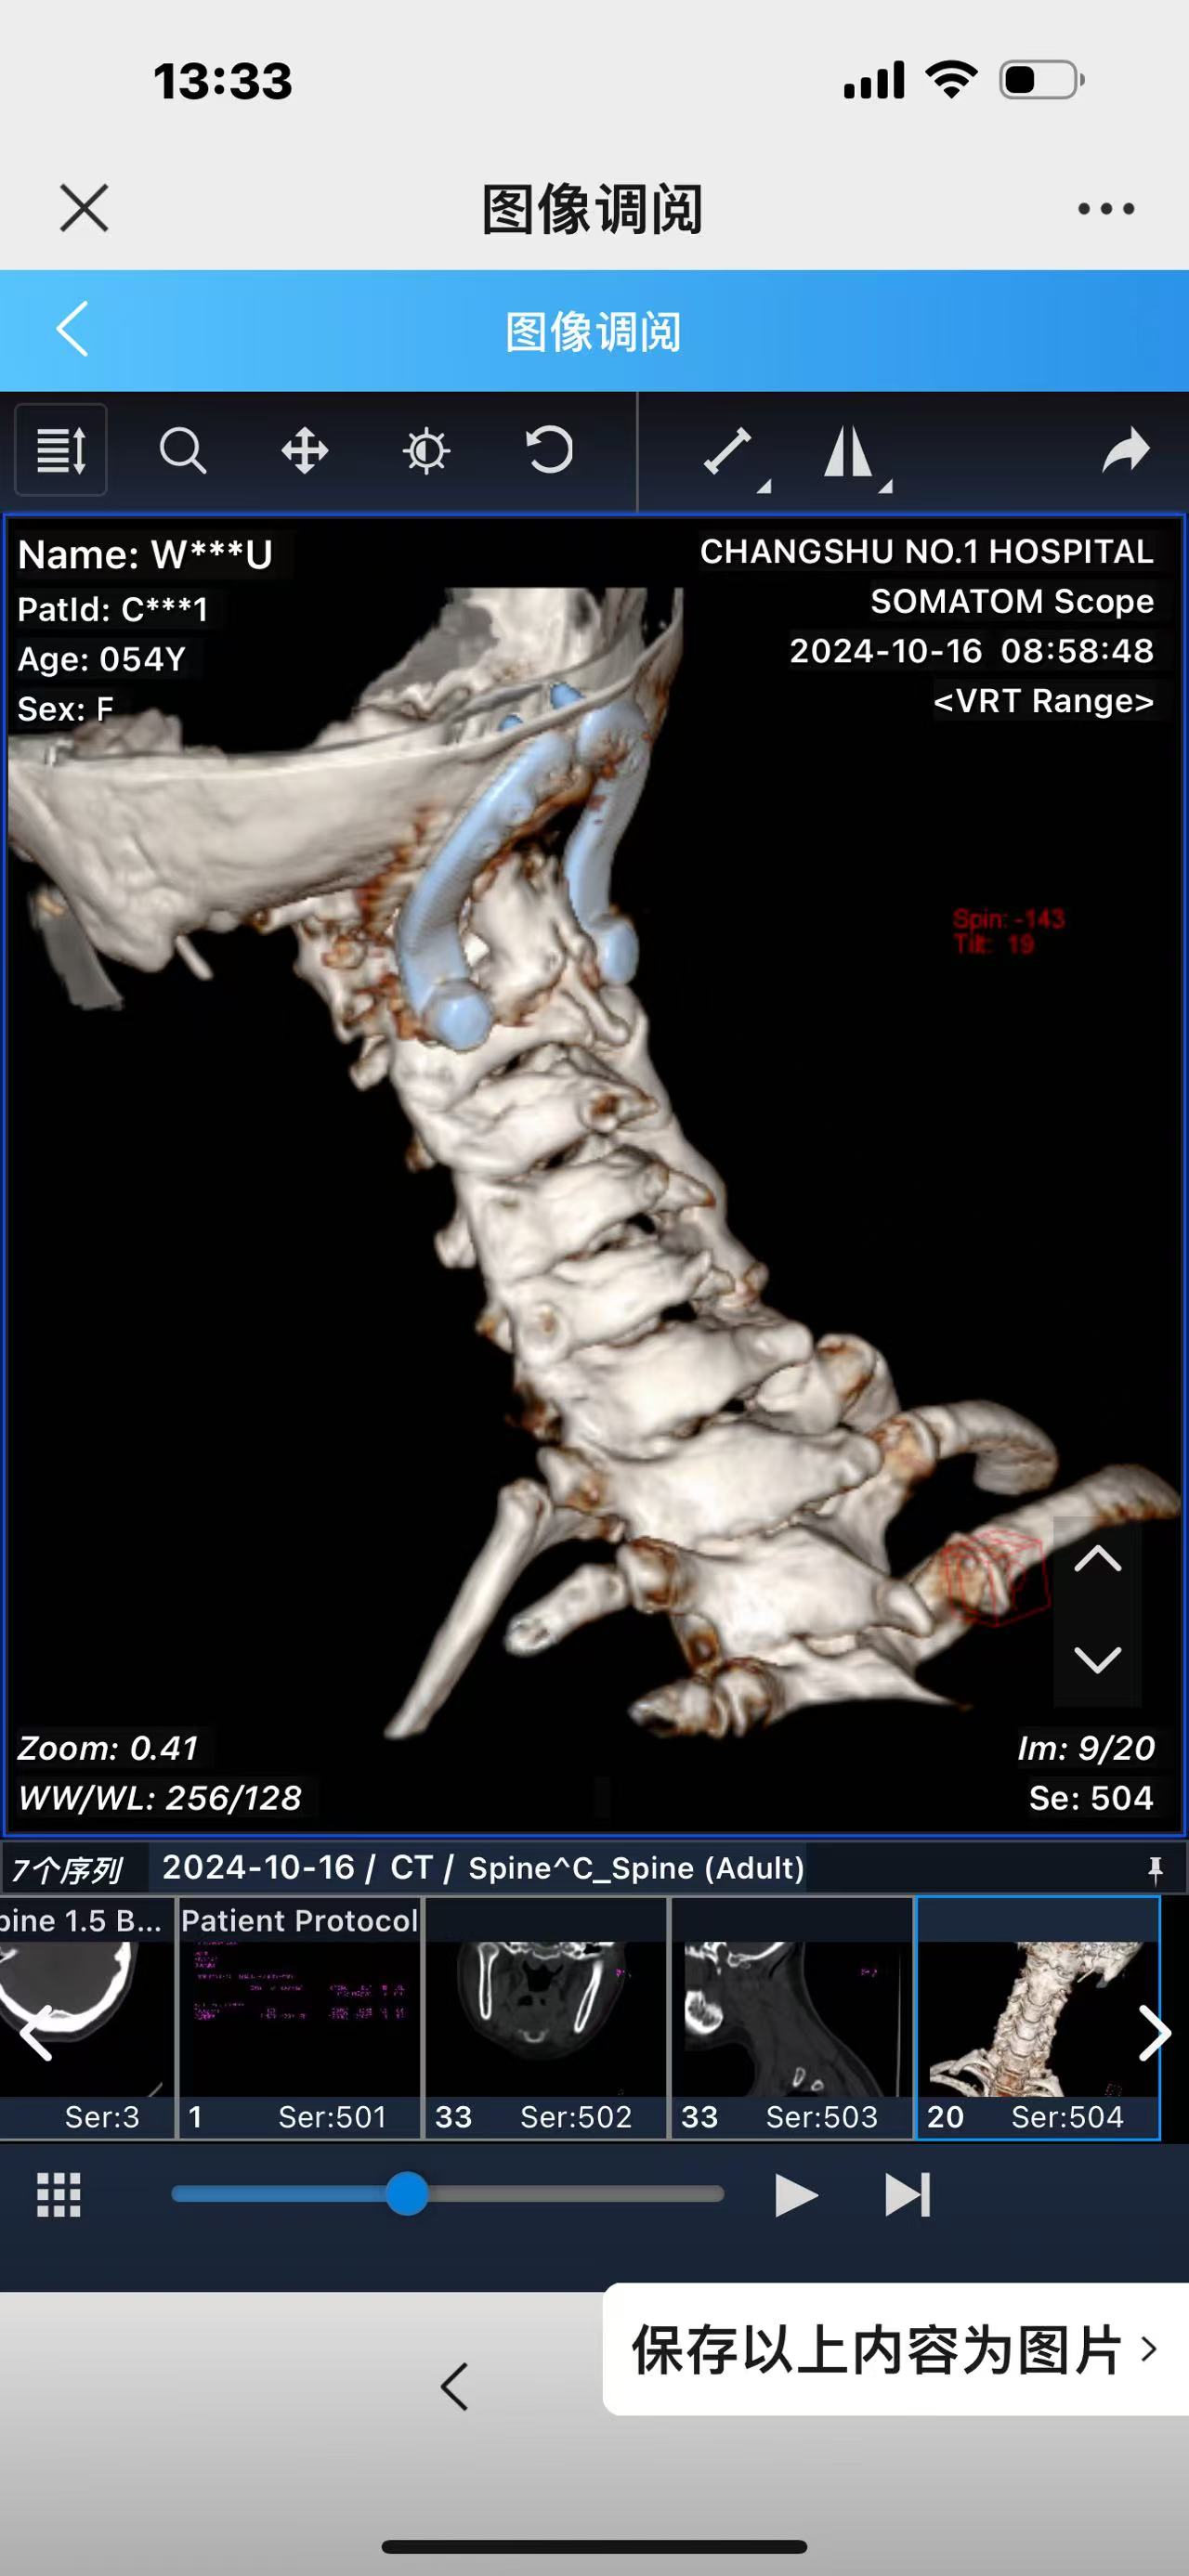

• 诊断:寰枢椎脱位,颅底凹陷

• 2024.10.20,复查,对位良好,偶尔会肩甲骨酸,坐下就不酸。